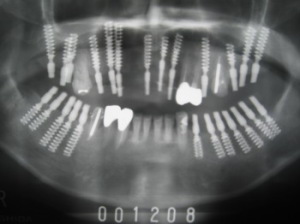

| 前歯が抜けてきた(動揺)として当院に来院 2000年10月27日 =解説= 奥歯に歯がないため、前歯に負担がかかって前歯が動揺 |